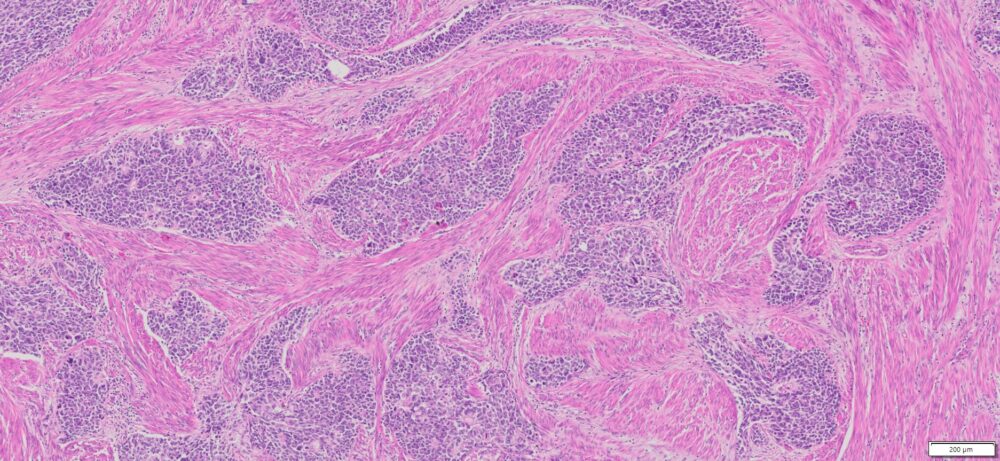

Description

| Organ& Tissue | Pathology Diagnosis | Gender/Age | % Tumor Area | Grade | TMN Stage | Biomarkers |

| Endometrial | Endometrial carcinosarcoma (malignant mixed Müllerian tumor) | Female/52 | 40% | NA | pT3apN1Mx | MLH1-2,MLH6 and PMS2: Intact nuclear expression |

More Images of H&E Stain and IHC